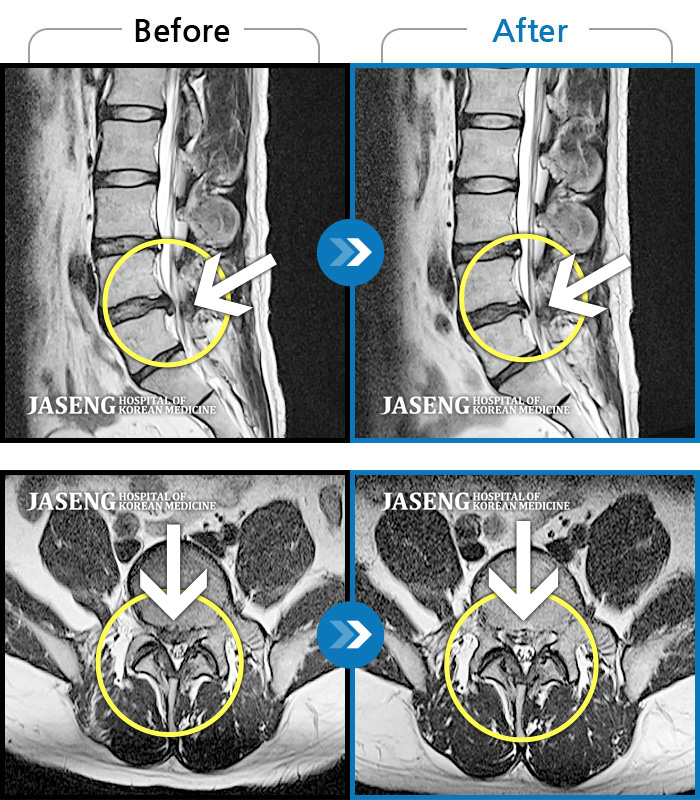

Before

After

환자에게 사전 동의를 받아 동일 조건에서 촬영되었습니다.

개인에 따라 치료 후 부작용이 발생할 수 있으니 의료진과 상담 후 치료를 진행하시기 바랍니다.

서서 움직일 때, 앉았다 일어날 때 허리 및 우측 다리 통증

허리 통증 및 몸이 앞으로 굽혀지지 않음